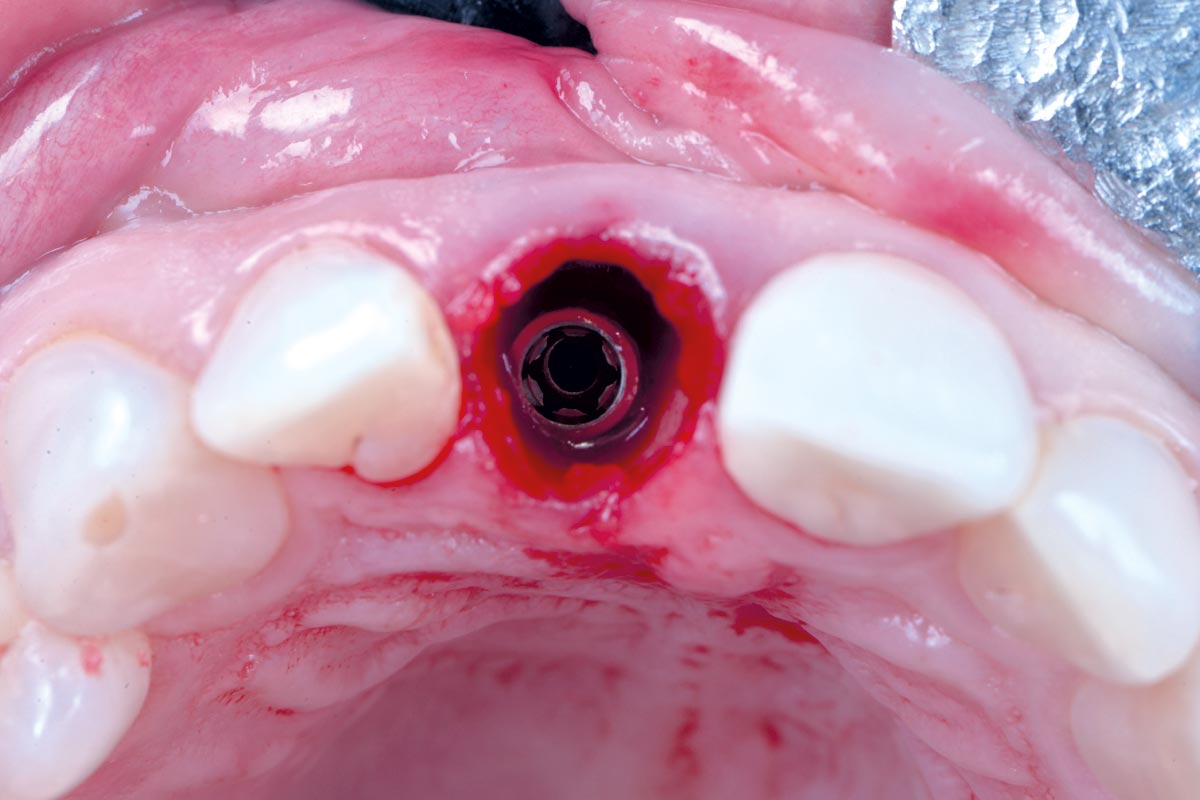

10/30 - Occlusal view – 4 mm placement depthExcellent aesthetic result of buccal augmentation with mucoderm® and maxgraft® after immediate implant placement - 3-years follow-up - Dr. A. Puišys